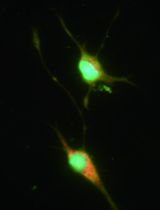

Immune cells, such as microglia are resident in the brain and spinal cord of normal mice and humans. Furthermore, macrophages, dendritic cells, T cells, B cells and NK cells infiltrate the CNS during certain infections or in neurodegenerative/neuroinflammatory diseases, such as experimental autoimmune encephalomyelitis (EAE) (a model for multiple sclerosis) or Alzheimer’s disease (Sutton et al., 2009; Browne et al., 2013). Infiltrating cells can be identified using immunohistological staining of sections from brain or spinal cords. However, more detailed phenotypic and functional analysis is possible following isolation of the immune cells from the CNS of normal or diseased mice. Purification of mononuclear cells from brain or spinal cord is dependent on perfusing the mouse to ensure removal of the blood from the CNS tissue, prior to dissociating the tissue and purification of the mononuclear cells on a percoll gradient. The technique provides single cell suspensions with cells of high viability that are suitable for FACS analysis or limited functional studies. The yields are usually low from the normal mouse brain or spinal cord, but higher from mice with EAE or CNS infection. When combined with intracellular cytokine staining and FACS, this technique is particularly useful for analysis of the pathogenic T cells (Th17 and Th1 cells) and their regulation/modulation in EAE.